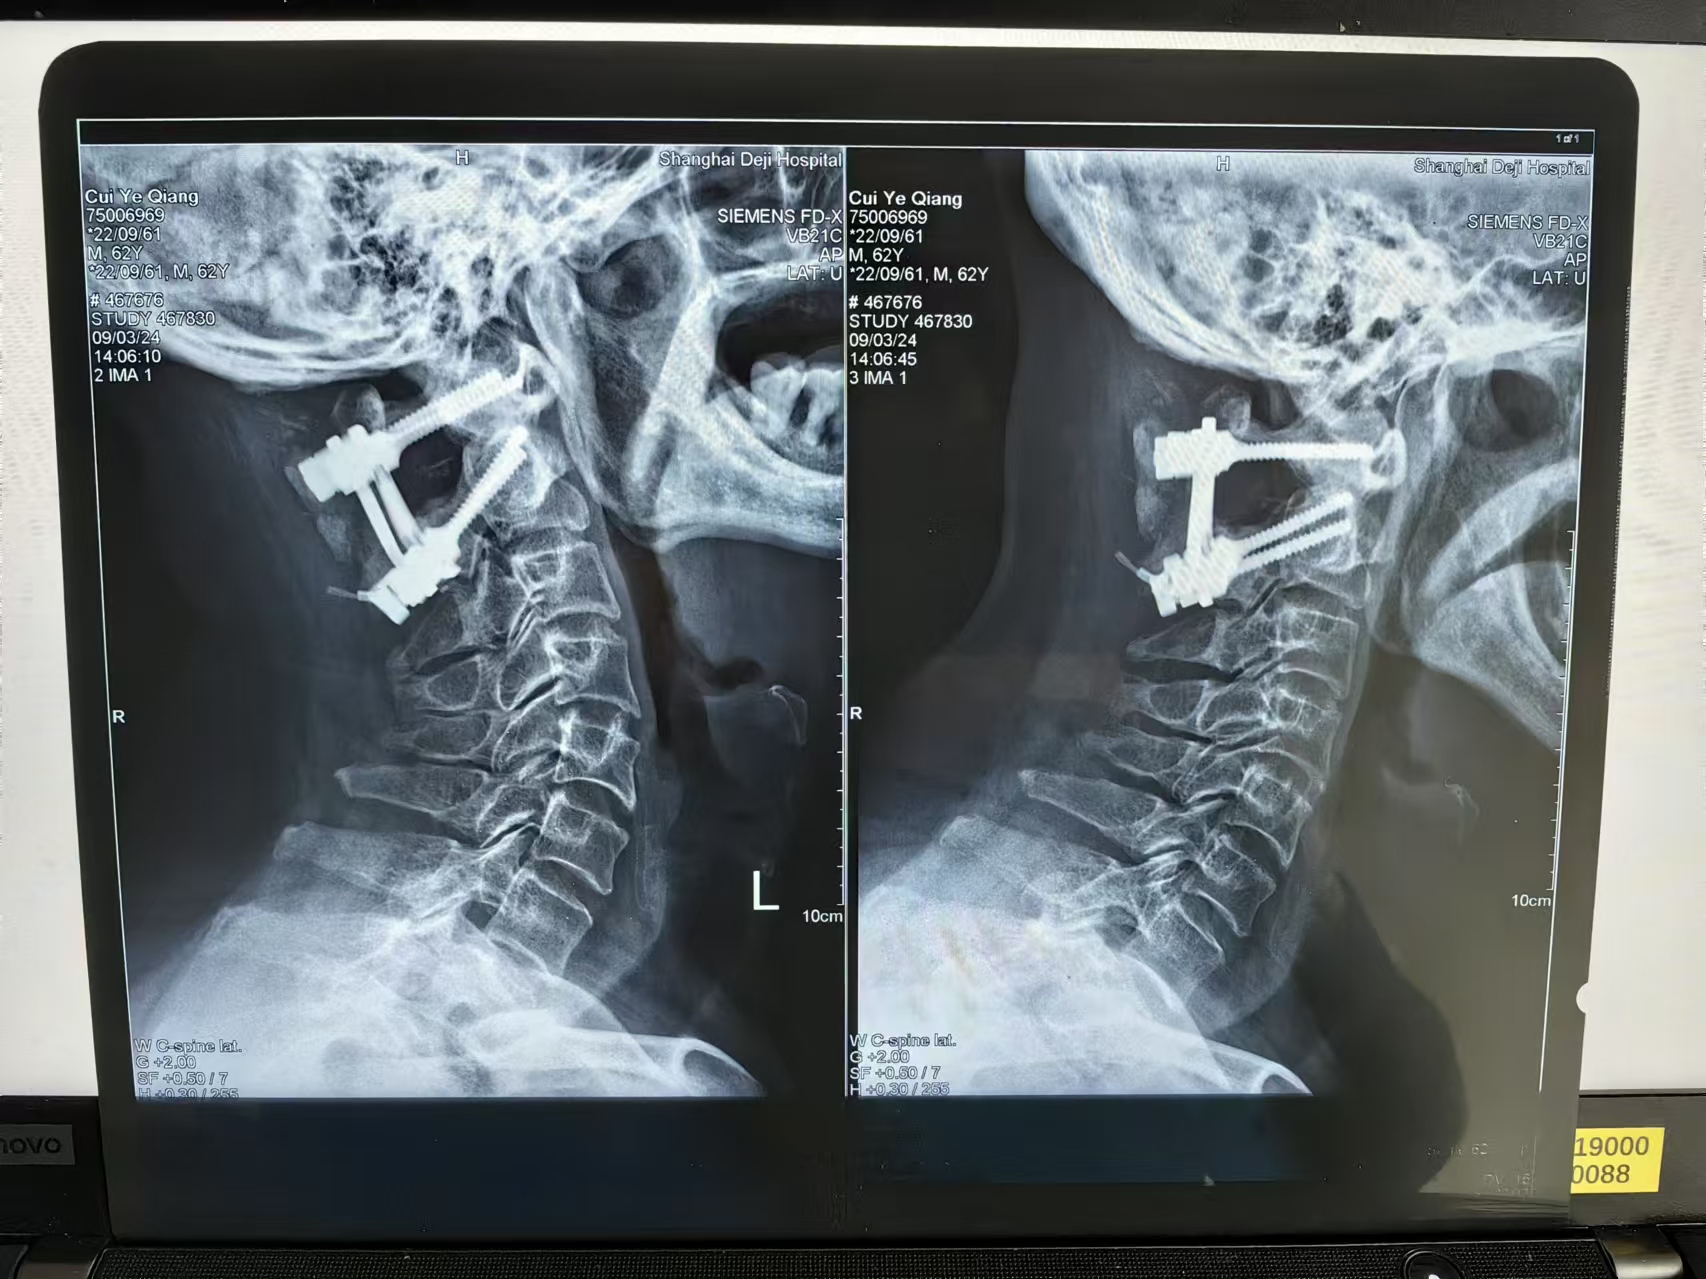

三次手术#

• 日期:2023.11

• 医院:北三医院

• 主刀:王超

• 术后影像:

• 2024.03.09,复查,对位良好,但术前症状难以恢复。